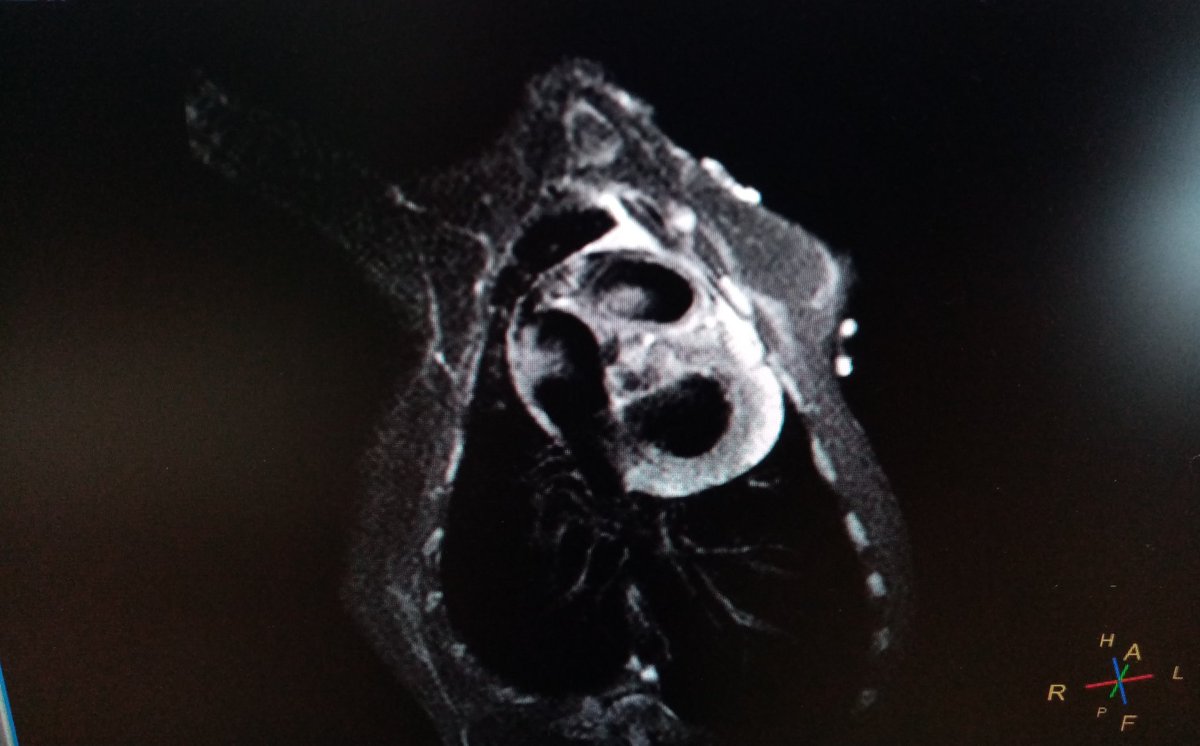

Our article "Intrapericardial delivery of APA-microcapsules as promising stem cell therapy carriers in an experimental AMI model" has been published in Pharmaceutics MDPI . @CIBER_CV Nanbiosis ICTS Jesus Ciriza Javier G Casado @CIBERBBN TME Lab UEx Cardiovascular_CCMIJU mdpi.com/1999-4923/13/1…

Our article "The epicardial delivery of CDCs or their extracellular vesicles is safe but of limited value in experimental infarction" has been published in Scientific Reports. Congrats! Carol Galvez-Monton Javier G Casado Toni Bayes Cardiovascular_CCMIJU @CIBER_CV Nanbiosis ICTS nature.com/articles/s4159…

New article!!"Intrapericardial Administration of Secretomes from Menstrual Blood-Derived Mesenchymal Stromal Cells: Effects on Immune-Related Genes in a Porcine Model of Myocardial Infarction" @HelenaFederica Javier G Casado CIBERCV Nanbiosis ICTS mdpi.com/2227-9059/10/5… MDPI

Our article "Effects of Cardiac Stem Cell on Postinfarction arrhythmogenic Substrate" has been published in IJMS MDPI as part of the Special Issue New Insights into Cardiovascular Diseases in Basic Research. Javier G Casado Ricardo Sanz-Ruiz JPortales mdpi.com/1422-0067/23/2…

Good news!Our scientific work "Intracoronary Administration of Microencapsulated HGF in a Reperfused Myocardial Infarction Swine Model" mdpi.com/2143662 #mdpijcdd has been published in JCDD MDPI Congrats Javier G Casado Alejandra Itziar Palacios Cardiovascular_CCMIJU @Rebeca_Blazquez